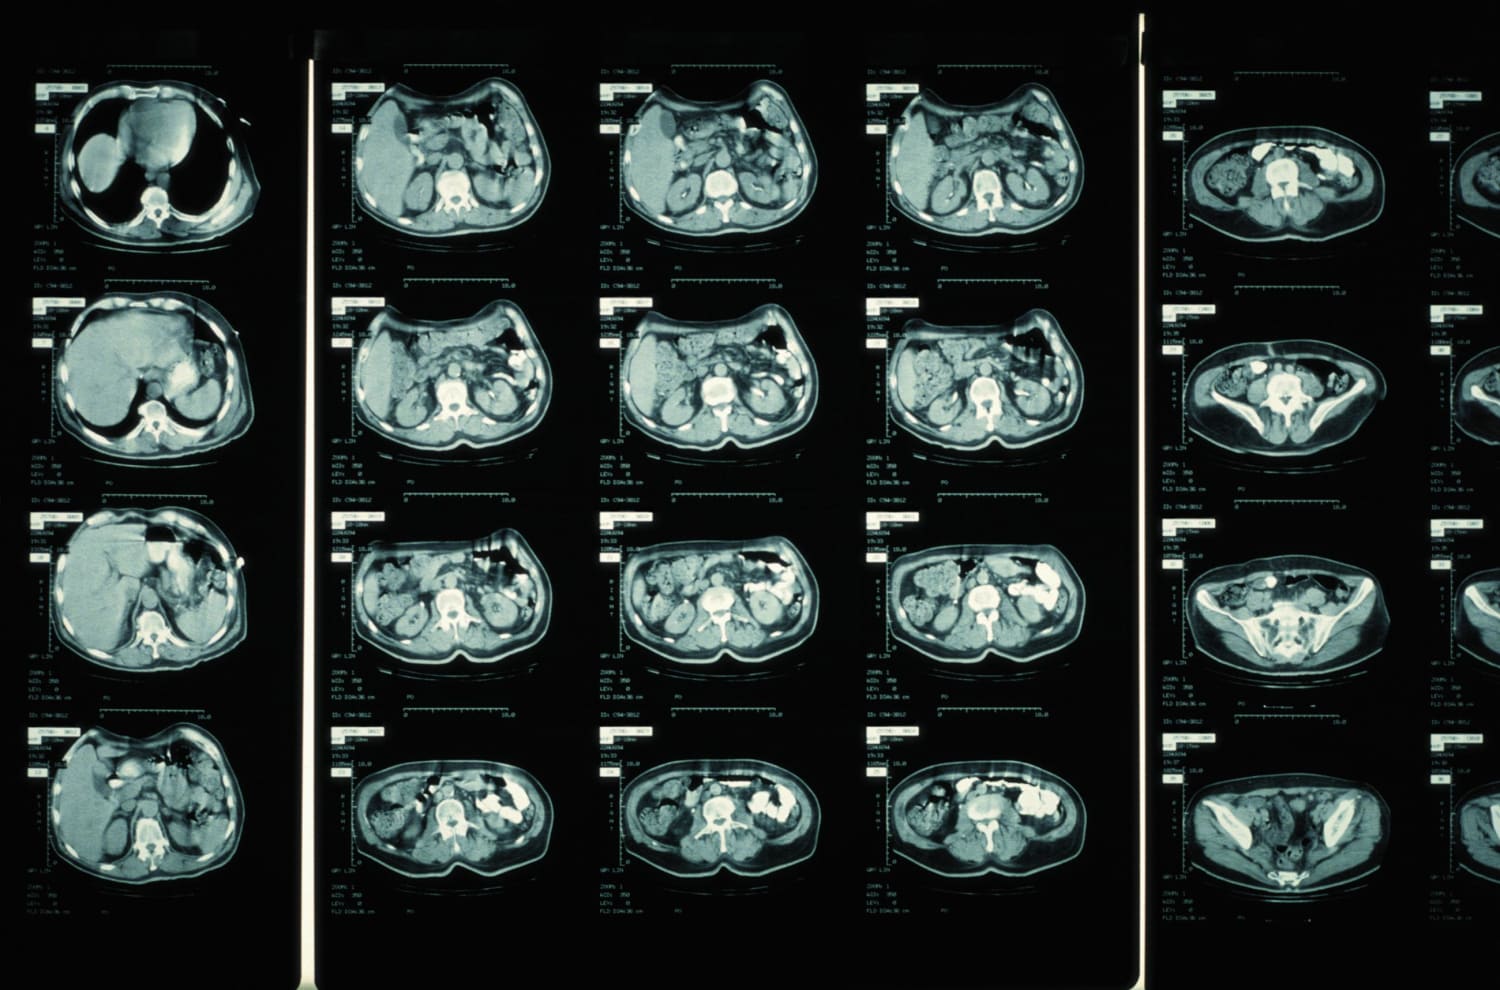

CT Scan (Computed Tomography "CAT Scan") | HSS Radiology

www.hss.edu

www.hss.edu

scans hss computed tomography

CT SCAN – Fairview Imaging Center

www.fairviewimagingcenter.com

www.fairviewimagingcenter.com

scan organs tomography computed